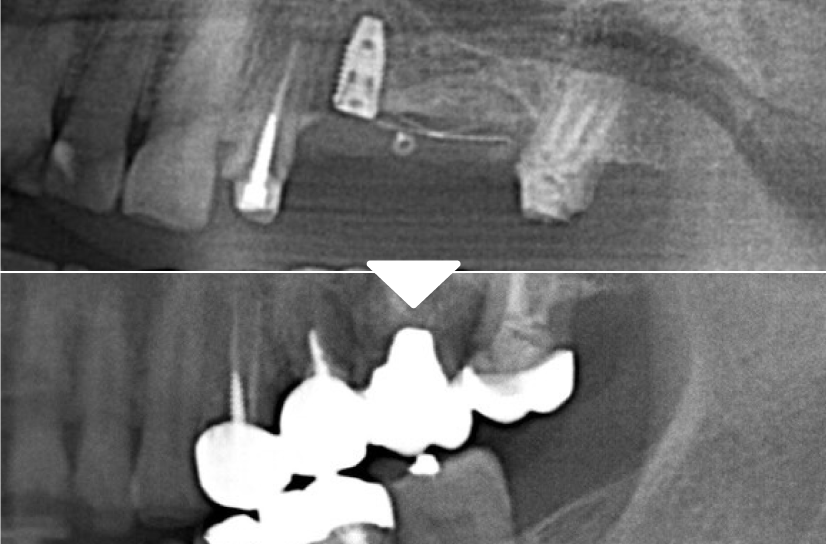

根管治療

右下7自費根管治療をし残すことができた症例です。他院で抜歯と診断を受けても自費根管治療だと残すことができる場合があります。

根管治療の症例

左下6自費根菅治療の症例。